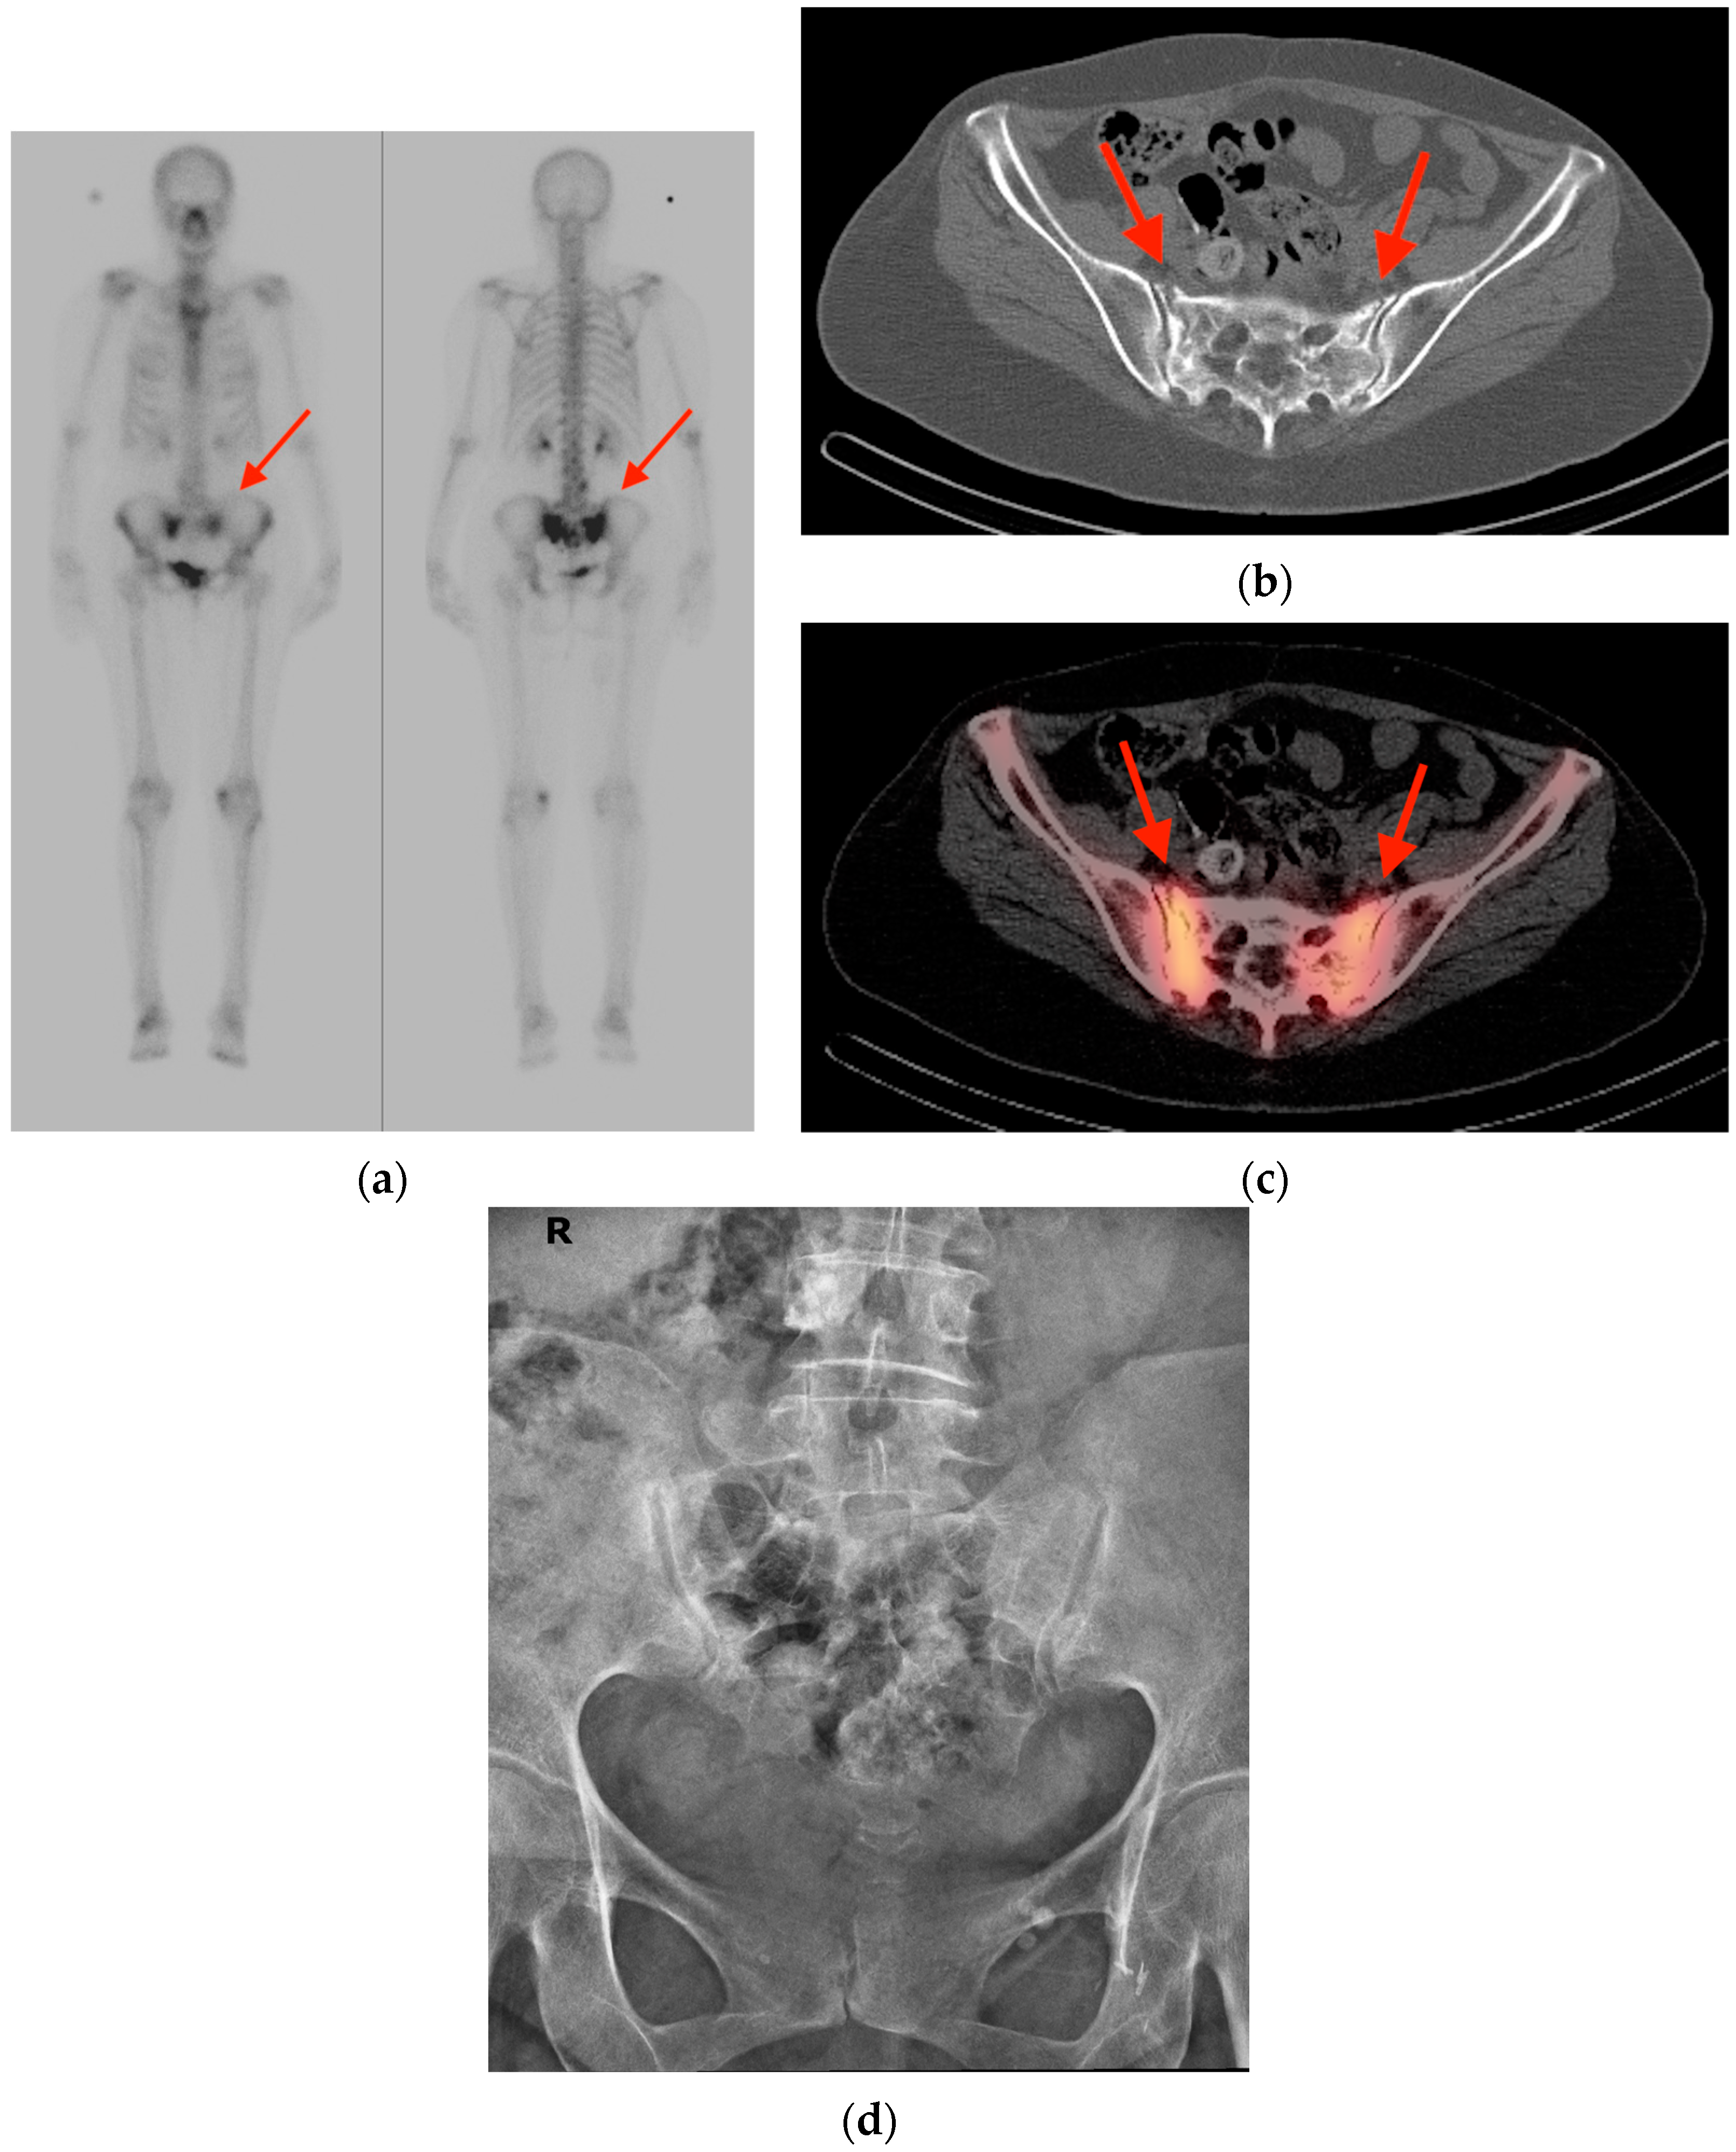

2.1. Fracture

- Chung, Y.K.; Lee, Y.K.; Yoon, B.H.; Suh, D.H.; Koo, K.H. Pelvic Insufficiency Fractures in Cervical Cancer After Radiation Therapy: A Meta-Analysis and Review. In Vivo 2021, 35, 1109–1115. [Google Scholar] [CrossRef]

- Abe, H.; Nakamura, M.; Takahashi, S.; Maruoka, S.; Ogawa, Y.; Sakamoto, K. Radiation-induced insufficiency fractures of the pelvis: Evaluation with 99mTc-methylene diphosphonate scintigraphy. AJR Am. J. Roentgenol. 1992, 158, 599–602. [Google Scholar] [CrossRef]

- Salavati, A.; Shah, V.; Wang, Z.J.; Yeh, B.M.; Costouros, N.G.; Coakley, F.V. F-18 FDG PET/CT findings in postradiation pelvic insufficiency fracture. Clin. Imaging 2011, 35, 139–142. [Google Scholar] [CrossRef]